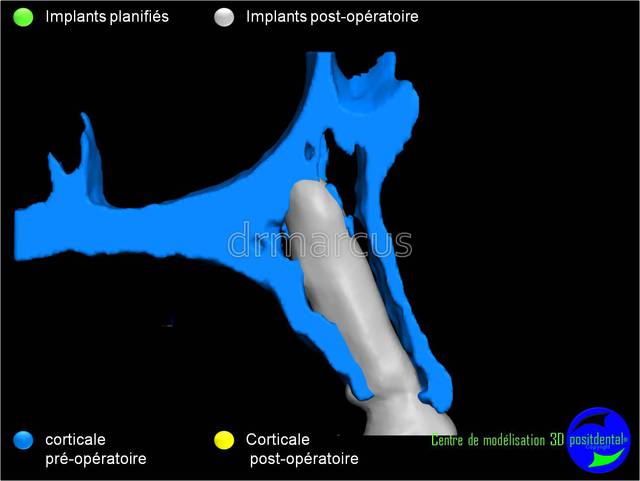

Analyse post-opératoire d’une MCI post-extractionnelle en chirurgie guidée

Cas clinique de drmarcus

Chirurgie : drmarcus

Imagerie 3D: POSITDENTAL

Guide chirurgical : POSITGUIDE

Dispositif de forage : POSITDENTAL

Implant : LEONE

Dommage que ce soit scanner avant et Cone-Beam après. Il est vrai que l’interprétation peut différer. Toutefois on voit la parfaite superposition des implants entre la planification et la réalisation. J'en conclue que le système Positdental est relativement fiable ;-))))